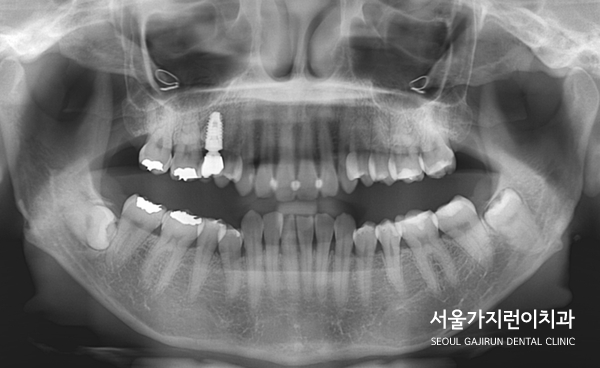

게다가 윗니에 임플란트까지 있는 케이스, 아랫니에는 사랑니도 있었는데요.

교정으로 할 때 임플란트의 존재와 임플란트 주변의 치아이동에 제한이 있다는 점을 염두하고 치아교정 계획을 수립해 진행하기로 했습니다. 또한 설측교정 방식을 적용해 치료를 진행했는데요. 두 개의 와이어로 설측탄댐교정을 진행해 치아이동에 필요한 힘을 안정적으로 주었습니다. 여기에 잇몸에 미니스크류를 식립해 고정원으로 삼고 이동을 시켰는데요.

임플란트한 치아가 움직이지 않도록 최대한 노력했고 다행히 임플란트도 이상 없이 유지되면서 교정을 마칠 수 있었습니다.

말끔하게 해결된 것을 확인할 수 있었습니다. 임플란트도 이상없이 안정적으로 유지된 것을 볼 수 있는데요.

엑스레이 상으로도 중첩되어있던 교합이 정상교합으로 돌아온 것을 확인할 수 있었습니다.